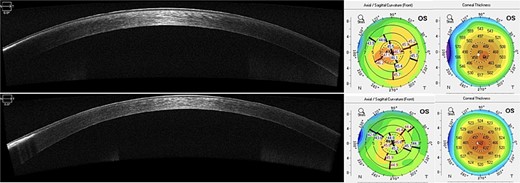

AS-OCT revealed an improvement in the hyper reflective band in the treated area. Scheimpflug imaging displayed superficial regularization and a predictable decrease in central corneal thickness of 20 μm (Fig. 4).

AS-OCT at 1-year postoperatively shows improvement of the paracentral hyper reflective band. A worsening in the peripheral untreated are can also be noticed. Scheimpflug imaging demonstrates thinning of central corneal thickness and reduction of mean anterior keratometry (45.3D) with superficial regularization.